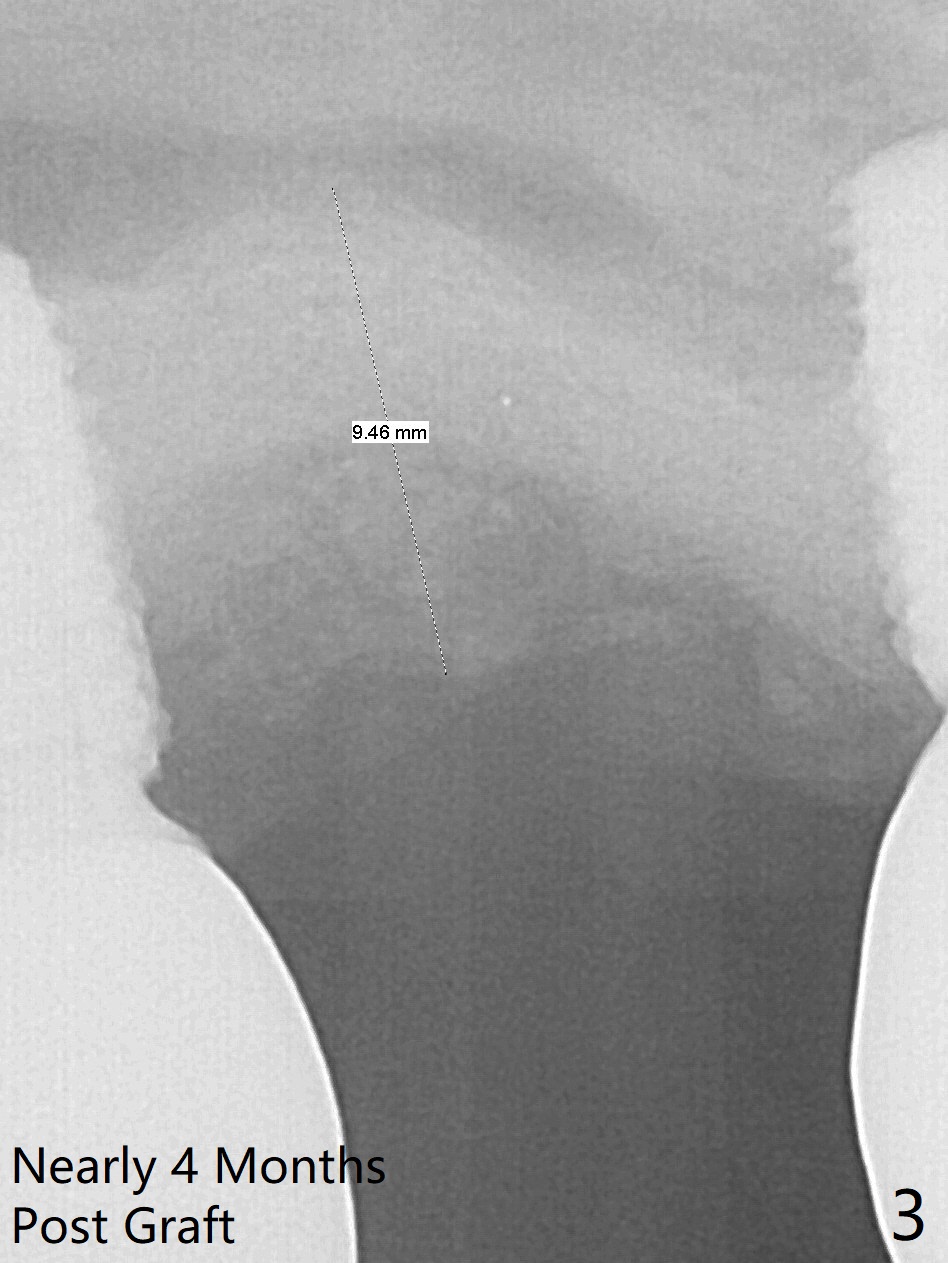

Removal of the implant at #2 is extremely difficult because of fusion of the abutment with the implant.  Buccal and palatal incisions are made to remove the bone buccomesiodistal to the implant.  After implant removal, the exposed mesial coronal implant threads at #1 are cleaned with Titanium brush; allograft is placed against the exposed threads (Fig.1 *), followed by 2 pieces of PRF membrane and 6-month collagen membrane.  Periodontal dressing is applied after suturing.  Partially due to traumatic implant removal and partially due to easy and repeated loss of periodontal dressing, bone height reduces nearly 4 months postop (compare Fig.2,3).  More discouraging is the invasion of loose nonkeratinized buccal gingiva into the healed socket nearly 4 months post graft (Fig.4 N).  Tissue punch thorough a guide should expose the implant site to the nonkeratinized tissue.  Can we fabricate a guide with buccal clearance underneath so that a flap can be raised buccally, i.e., to push the palatal keratinized tissue buccally?